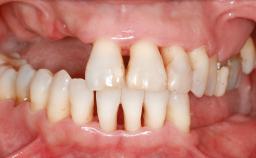

Guided Bone Regeneration (GBR) with a Particulated Autologous Graft and a ePTFE-Reinforced Membrane for Vertical Augmentation of a Single-Tooth Edentulous Space in the Esthetic Zone

A 47-year-old Caucasian woman with a single-tooth edentulous space at the site of the left maxillary canine was referred for treatment. She had undergone traumatic extraction of this impacted canine several months before referral. Her chief complaint was the dissatisfying appearance of her smile. The patient desired a stable and esthetic rehabilitation of the site. Her dental history showed no evidence of periodontal disease or bruxism. She had no systemic diseases, was not taking any medications, and did not smoke. The extraoral examination revealed a high lip line and an inadequate soft-tissue volume at the defective canine site. Large black triangles were visible between the canine and its adjacent teeth.

Soft Tissue Anatomy Intact Defective

Bone Volume Horizontally and vertically sufficient Horizontally deficient Deficient vertically or deficient vertically AND horizontally